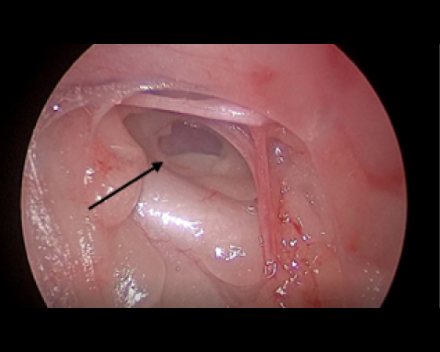

胸腔鏡で覗くと胸管がキレイに見えます(黒矢印)。

これを鉗子で丁寧に剥離していきます

反対側も同じように剥離していきます。

必ず、反対側の胸管も確認できるところまで剥離します。(黒矢印)

反対側もクリップ3-4本止めて、結紮します。

これで胸管結紮は終了です